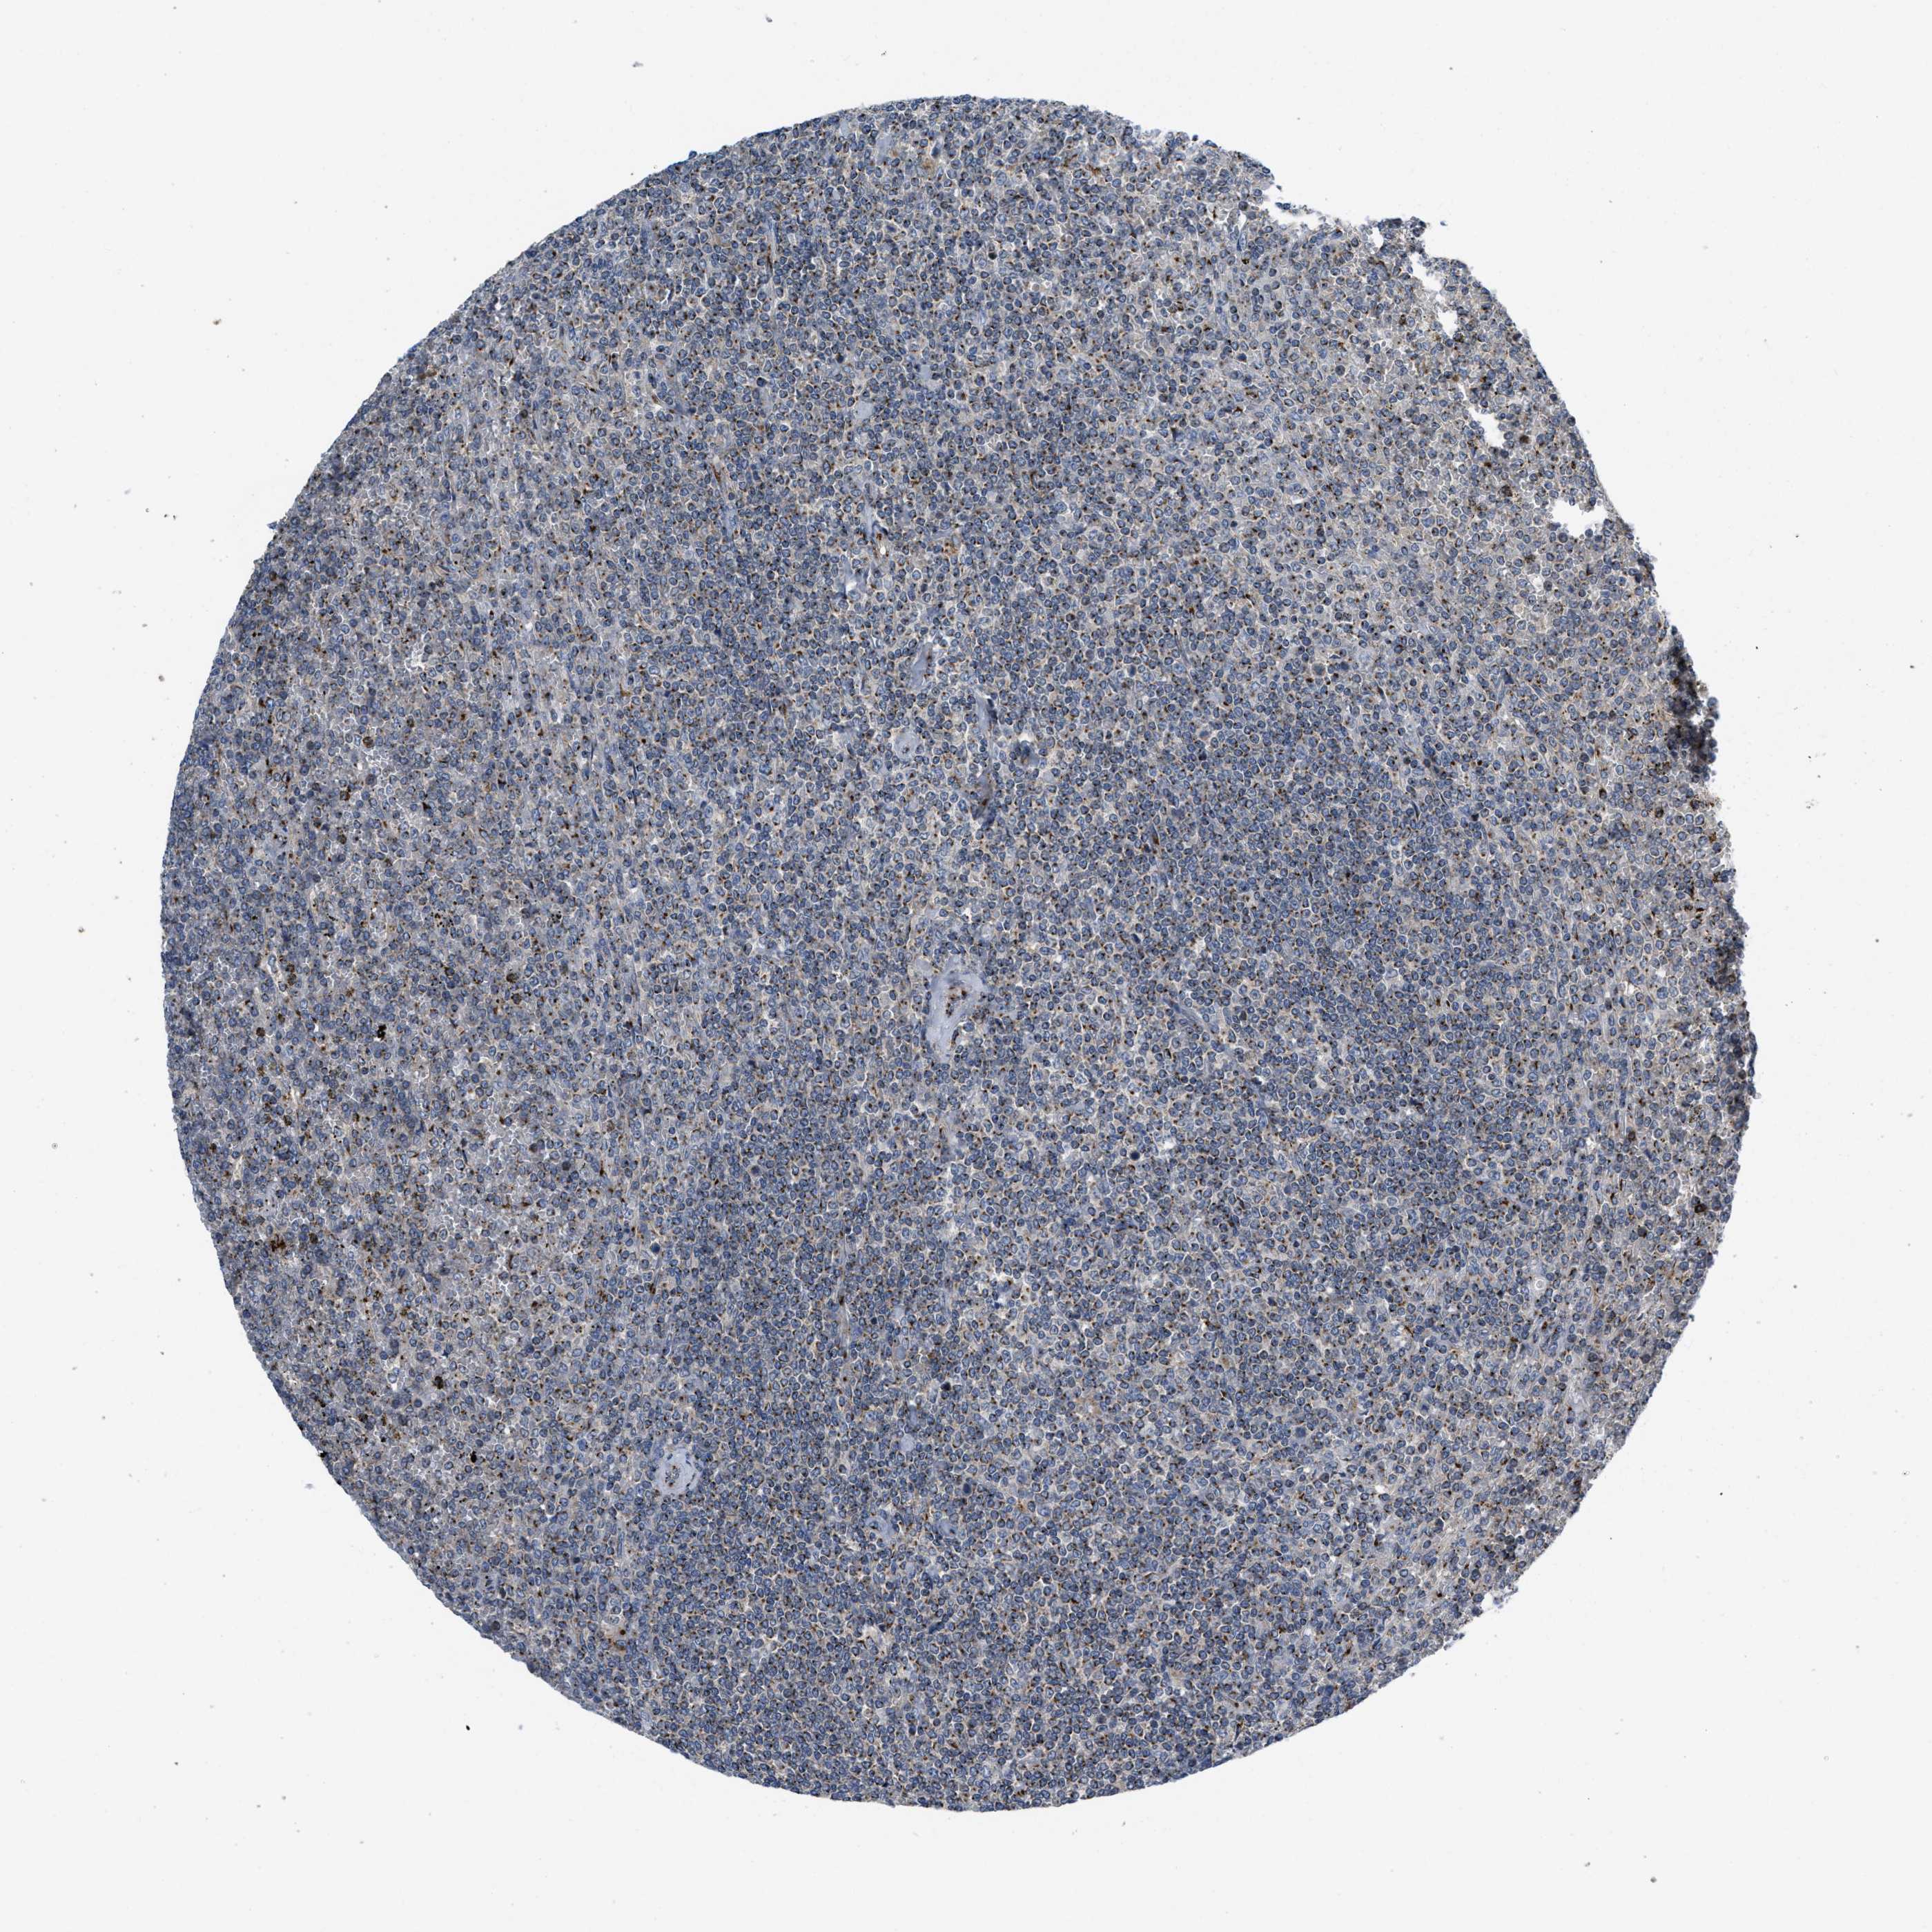

CANCER LYMPHOMA Show tissue menu

LYMPHOMA - Protein expressioni

A mouse-over function shows sample information and annotation data. Click on an image to view it in a full screen mode. Samples can be filtered based on level of antibody staining by selecting one or several of the following categories: high, medium, low and not detected. The assay and annotation is described here.

Each image is clickable and will lead to virtual microscopy that enables deeper exploration of all samples and also displays staining intensity scores, fraction scores and subcellular localization as well as patient and tissue information for each sample.

Antibody HPA018821

Hodgkin's disease, NOS

Malignant lymphoma, non-Hodgkin's type, High grade

Malignant lymphoma, non-Hodgkin's type, Low grade